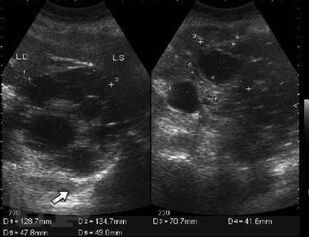

В Практическом руководстве отражены вопросы клинико-лабораторно-лучевой диагностики эхинококкоза печени с сипользованием УЗИ, РКТ, МРТ и современные аспекты лечения. Практическое руководство предназначено для специалистов лучевой, клинической, лабораторной диагностики, терапевтов, гепатологов, хирургов, онкологов.